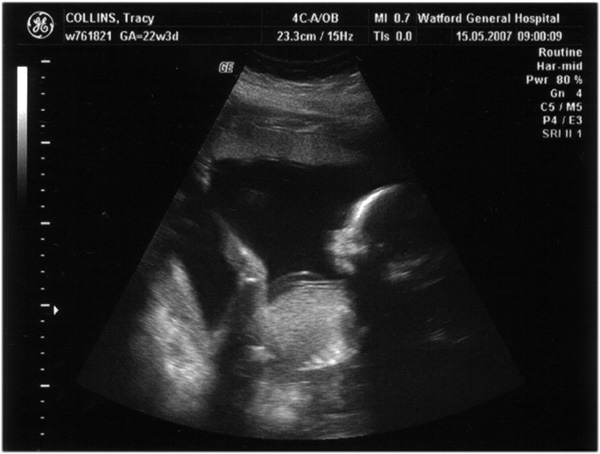

Third scan, 15th May 2007, (21 weeks)